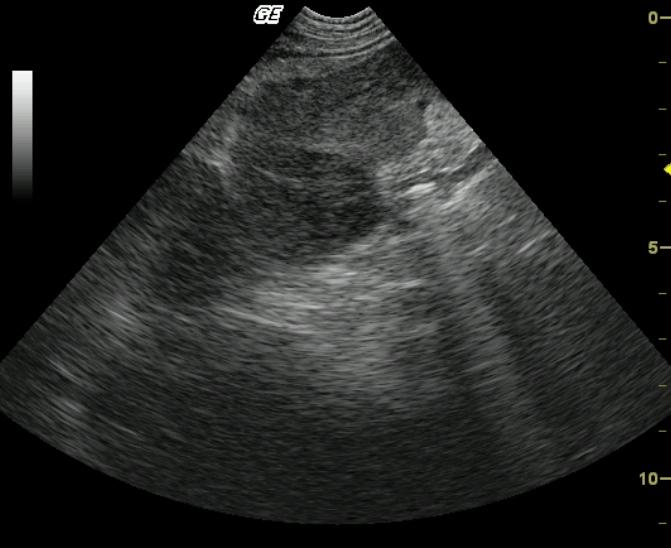

Coarse architecture is noted in both the spleen and liver with irregular capsular contour, echogenic and irregular tissue striations with nodular changes. This universal deviation from parenchymal architecture in both organs suggests a neoplastic process in both liver and spleen. The linear echogenic focus in the near field is a core biopsy needle.

Infiltrative and sclerosing splenic and hepatic pathology, likely neoplastic. Minor potential for aggressive inflammatory disease.

Fibrosarcoma, liver and spleen